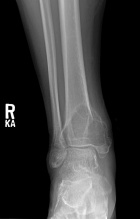

30 year old male with six month history of ankle pain, swelling; ambulates with a limp

Zoom image: Radiological image Radiological image.